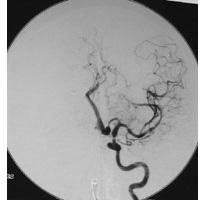

頻繁に右半身の一過性片麻痺(脳虚血発作)を繰り返した左内頚動脈閉塞症例

将来的に大きな脳梗塞の発症が危惧されたため、頭皮の血管を脳の血管につないで血液を補給するバイパス手術 EC-IC bypass)を施行しました。術後、吻合した血管が脳に血流を送っていることが確認されました(矢印)。